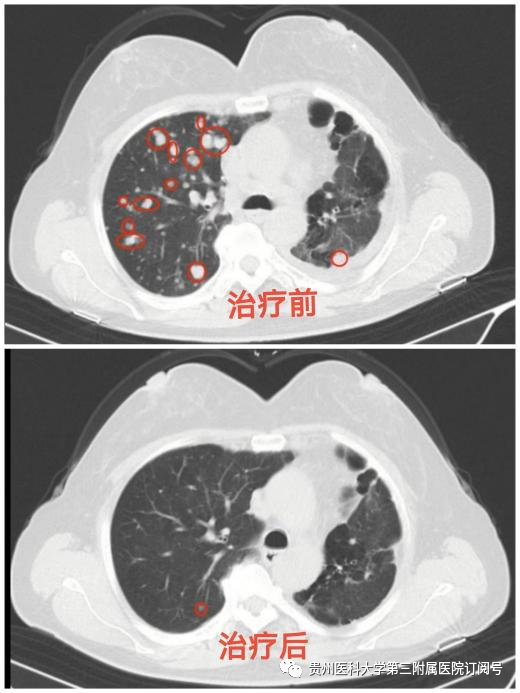

功夫不负有心人,经过肿瘤科的精心治疗和悉心护理,黄女士咳嗽、咳痰、胸痛、胸闷及呼吸困难已基本缓解,复查胸部CT提示多处病灶均较前明显缩小,精神状态明显好转。